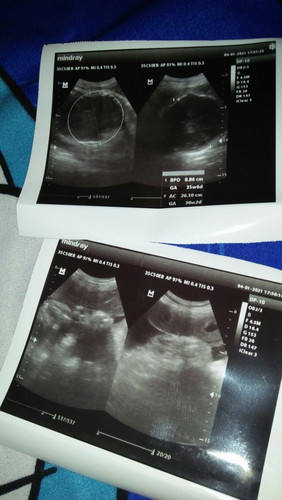

Hamil 35 minggu lebih tp plasenta udah pengapuran. Hamil pertama, gimana yah bunda aku takut kenapa2